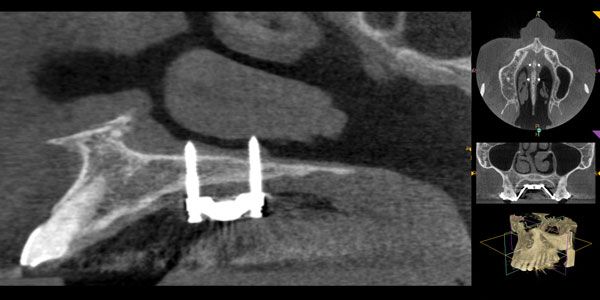

Combining accelerated orthodontics with orthognathic surgery to reduce overall treatment time

Dr. David Alpan discusses how smart mechanics with accelerated orthodontics facilitates an improved clinical outcome in shorter time with less negative sequelae Abstract Reducing the pre-surgical orthodontic phase with accelerated orthodontics leads to a shorter overall treatment time.21,22,23,24 Planning orthognathic surgery with 3D virtual diagnostic setups can help predict the clinical challenges, which help reduce […]